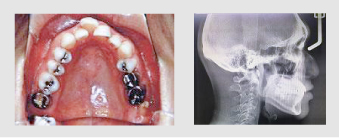

症例

上下の歯型、レントゲン3枚、お口の中のお写真をとります。